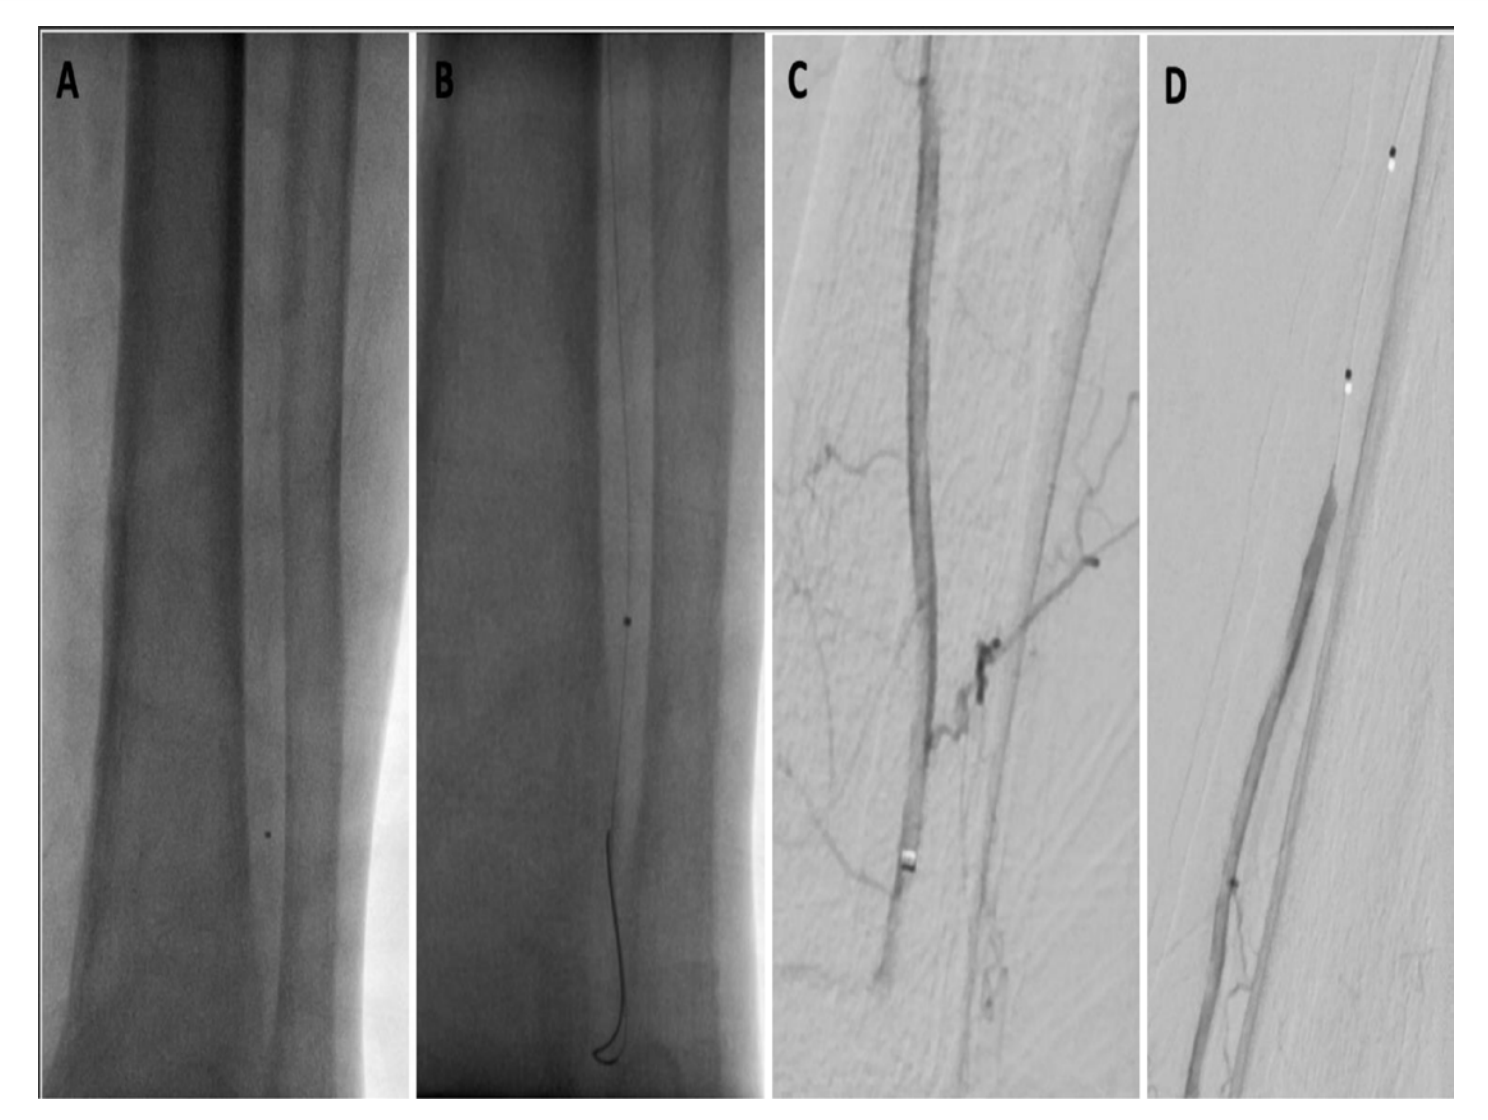

A third, final option was to perform embolectomy at this location, using an over-the-wire mechanical aspiration with a CAT3 catheter (Penumbra). After a single pass, there was flow restored to most of the distal peroneal artery, but a second pass was required in order to restore flow into the perforating branch of the peroneal artery (Figure 5). When the catheter was externalized from the groin sheath, physical exam demonstrated an unwound coil and no radiopaque marker band, consistent with shearing of the catheter tip (Figure 6). Although there was no significant resistance when removing the catheter, findings were confirmed on spot view of the ankle, which showed the radiopaque tip wedged within the perforating branch of the peroneal artery (Figure 7).

Despite successful embolectomy, attention was now drawn to foreign body retrieval. Initial attempts were performed under the basis of threading a wire though the catheter tip containing the radiopaque marker band and using a small-diameter balloon to fixate the device for retrieval (a “thread the needle” approach). However, the .014-inch wire could not be advanced through the lumen of the radiopaque band, but instead, could only be advanced beside the marker band. A repeat angiogram was performed that revealed the underlying issue: a thin radiolucent defect was noted in the peroneal artery, consistent with a much longer segment than expected for the catheter fragment (Figure 7). Multiple angiograms were performed in a stepwise, cephalad fashion in order to determine the location of the proximal catheter fragment. However, once in the larger diameter popliteal artery, it was difficult to delineate the catheter. Multiple spot views and oblique digital subtraction angiograms still could not delineate the radiolucent catheter.

An astute team member brought up the idea of using ultrasound to identify the fluoroscopically radiolucent catheter. Therefore, intravascular ultrasound (Philips) was performed, and easily and accurately demonstrated the proximal tip to be within the mid superficial femoral artery, a few centimeters distal to the sheath (Figure 8). Using a 15 mm loop snare, the catheter fragment was successfully retrieved, completely intact (Figure 9). The final angiogram demonstrated completely restored flow through the personal artery, with reconstituted pedal arteries (Figure 10). The patient’s foot was warm and her pain had resolved. There were no signs of compartment syndrome after flow was restored.